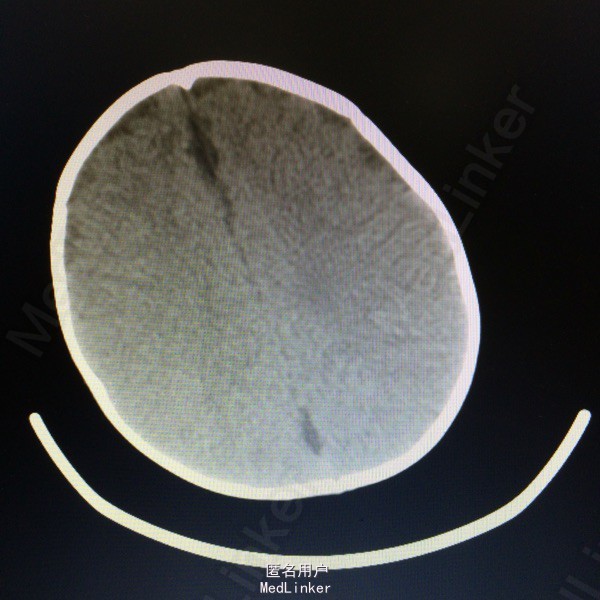

查体:枕后部肿物 辅助检查:行头颅MR提示顶针部中线异常信号,多考虑脑膜膨出

诊断:脑脊膜膨出 处理:枕部脑膜膨出囊切除术➕硬脑膜修补术